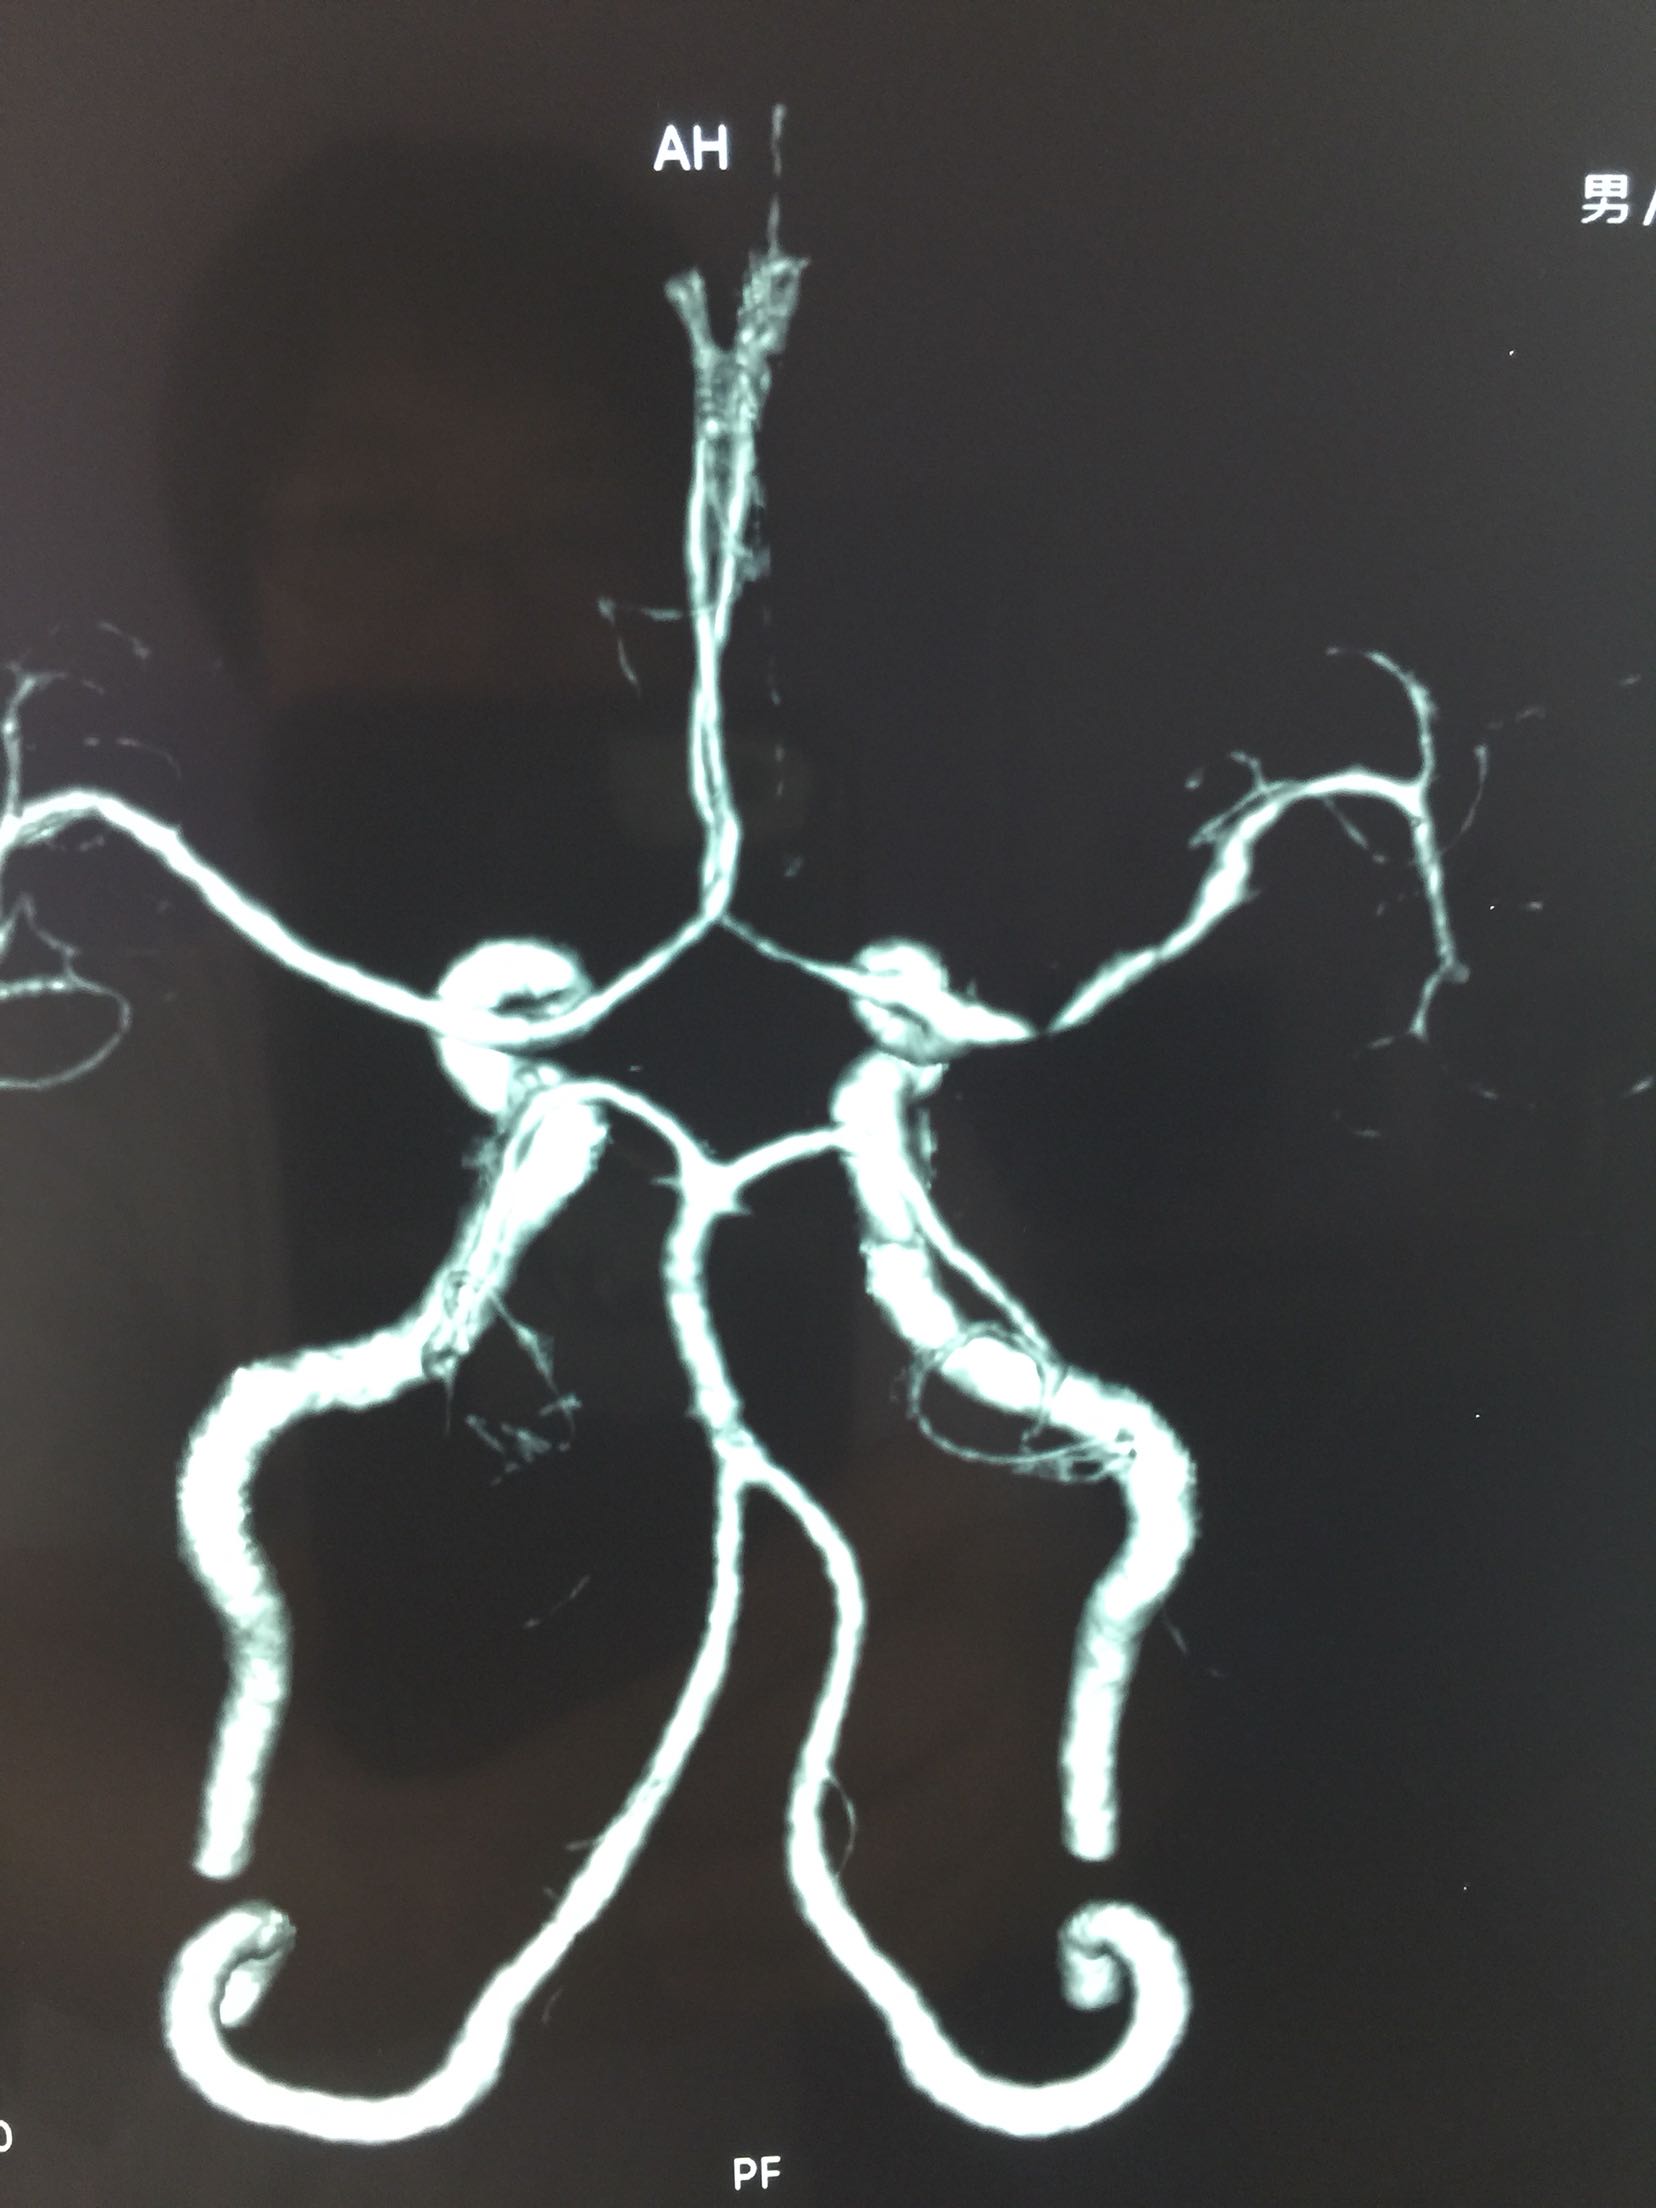

查体:T:36.5℃ P:68次/分 R:18次/分 Bp:120/70mmHg 内科系统:正常 神经系统:神志清楚,言语欠流利,查体合作,平车推人病房。左侧鼻唇沟浅,伸舌左偏,左侧肢体肌力0级,左侧肢体腱反射消失,左巴士征阳性。 辅助检查:血尿常规:正常 肝功、生化:正常 LDL-ch:5.12mmoL/l 心电图:窦性心律 头MRI+MRA、头CTA:

见下图

诊断:脑梗死 右侧大脑中动脉M1段重度狭窄 治疗:阿替普酶溶栓 醒脑静营养神经 长春西汀改善循环 丁苯肽建立侧枝循环 24小时后阿司匹林 氯比格雷抗血小板 瑞舒伐他汀降脂稳定斑块